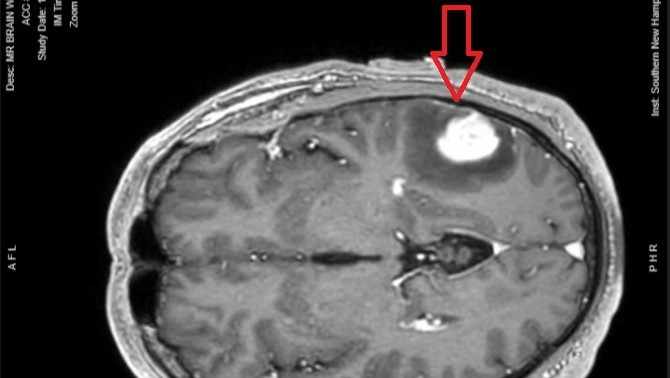

On May 13, 2024 Steve was in an online meeting with co-workers when he suddenly found himself unable to spell basic words. He thought he was simply overtired but the symptoms persisted into the following day so he went to the emergency room. After a battery of tests, they eventually discovered a mass on his brain which was putting pressure on the part of the brain utilized for spelling and word recall. From there, everything was a whirlwind. He quickly scheduled brain surgery for May 22 at Massachusetts General Hospital. The tumor was removed and his word recall issues were resolved, but pathology tests revealed a diagnosis of Glioblastoma (aka “GBM”) which is the most aggressive form of brain cancer.

Unfortunately, with GBM, it is inevitable that tumor growth will eventually return and be more resistant to treatments. Bi-monthly MRI’s will be required for the rest of Steve’s life to monitor for any new tumor growth. Some people call it “scanxiety” because it’s impossible to predict when the tumor will return. The average lifespan for a GBM patient is only 14 months, but Steve is pursuing every possible avenue to beat the odds. He’s had some emotional days, but for the most he’s remained remarkably positive and focused.